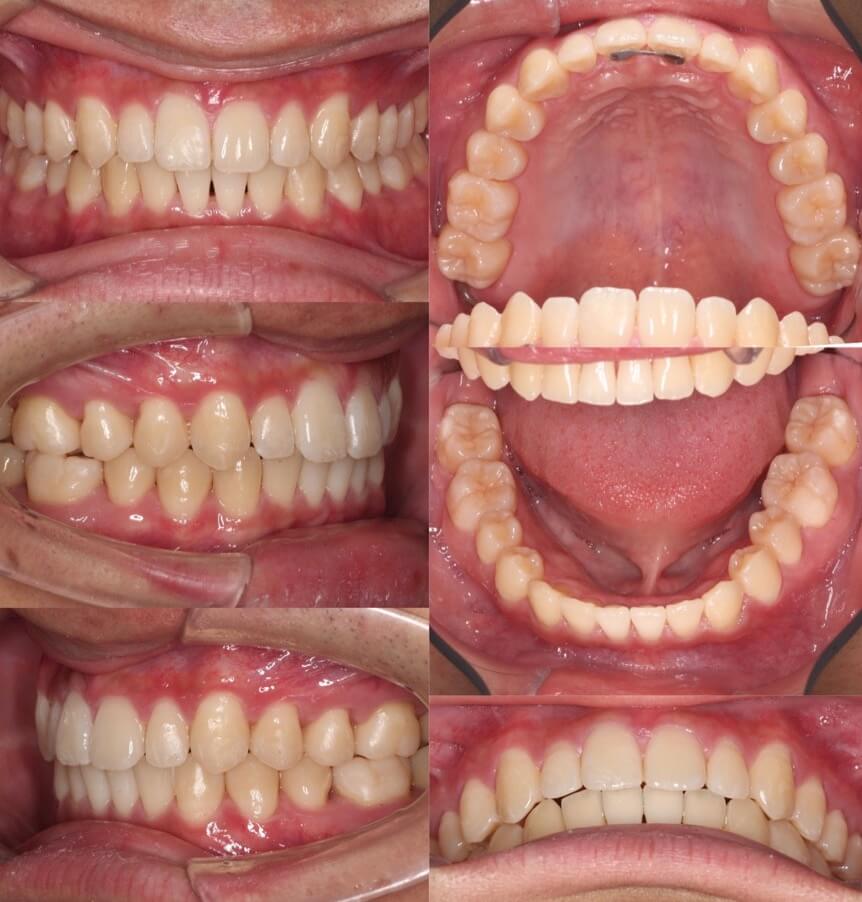

高校生男子・マウスピース型矯正装置

<症例概要>

主訴:すきっ歯

年齢・性別:高校生男子

症状:正中離開・過蓋咬合

治療方針:空隙閉鎖+下顎歯列前方移動

治療装置:マウスピース型矯正装置(アライナー装置)

固定装置:II級顎間ゴム

治療期間:1年7か月

アライナー枚数:58+26ステージ (7日交換)

リテーナー:上フィックスタイプ+上下クリアタイプ

治療費用:990,000(税込)

隙間が上下奥歯まであり難しいケースになります。このような出っ歯傾向がある空隙歯列は、マウスピース型矯正装置の適応症です。また、10代男子であればあご骨格の成長量が残っており利用して前歯の前突の改善もできます。過蓋咬合も治り、スマイルの印象も変わりました。